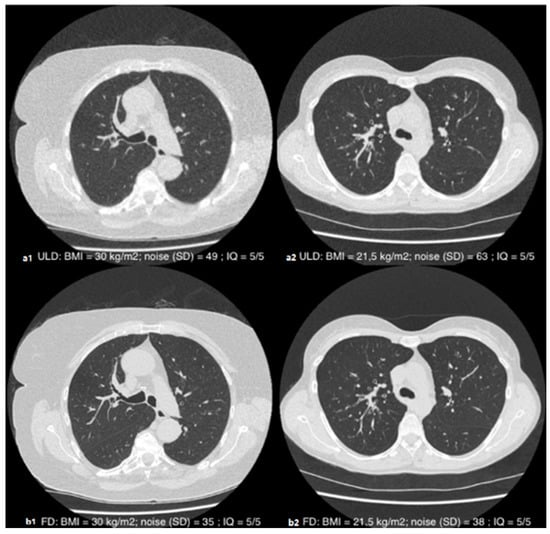

3.4. Subjective Image Quality